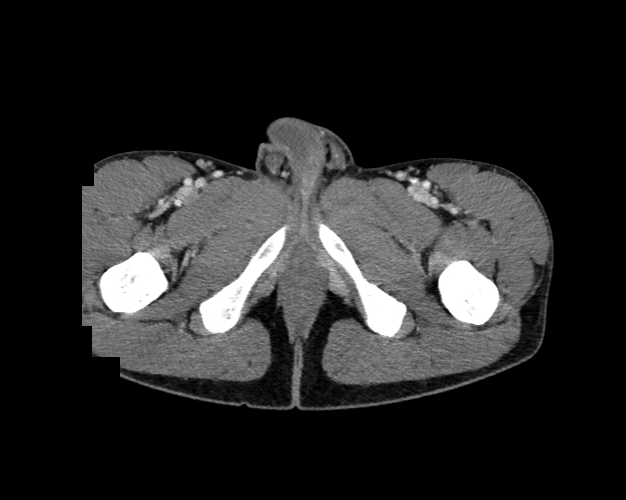

Body

Covers abdominal CT anatomy.

Pelvis

Covers pelvic MRI anatomy.